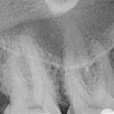

Preoperative x-ray of a 16 and a 17, both with deep caries and acute pulpitis.